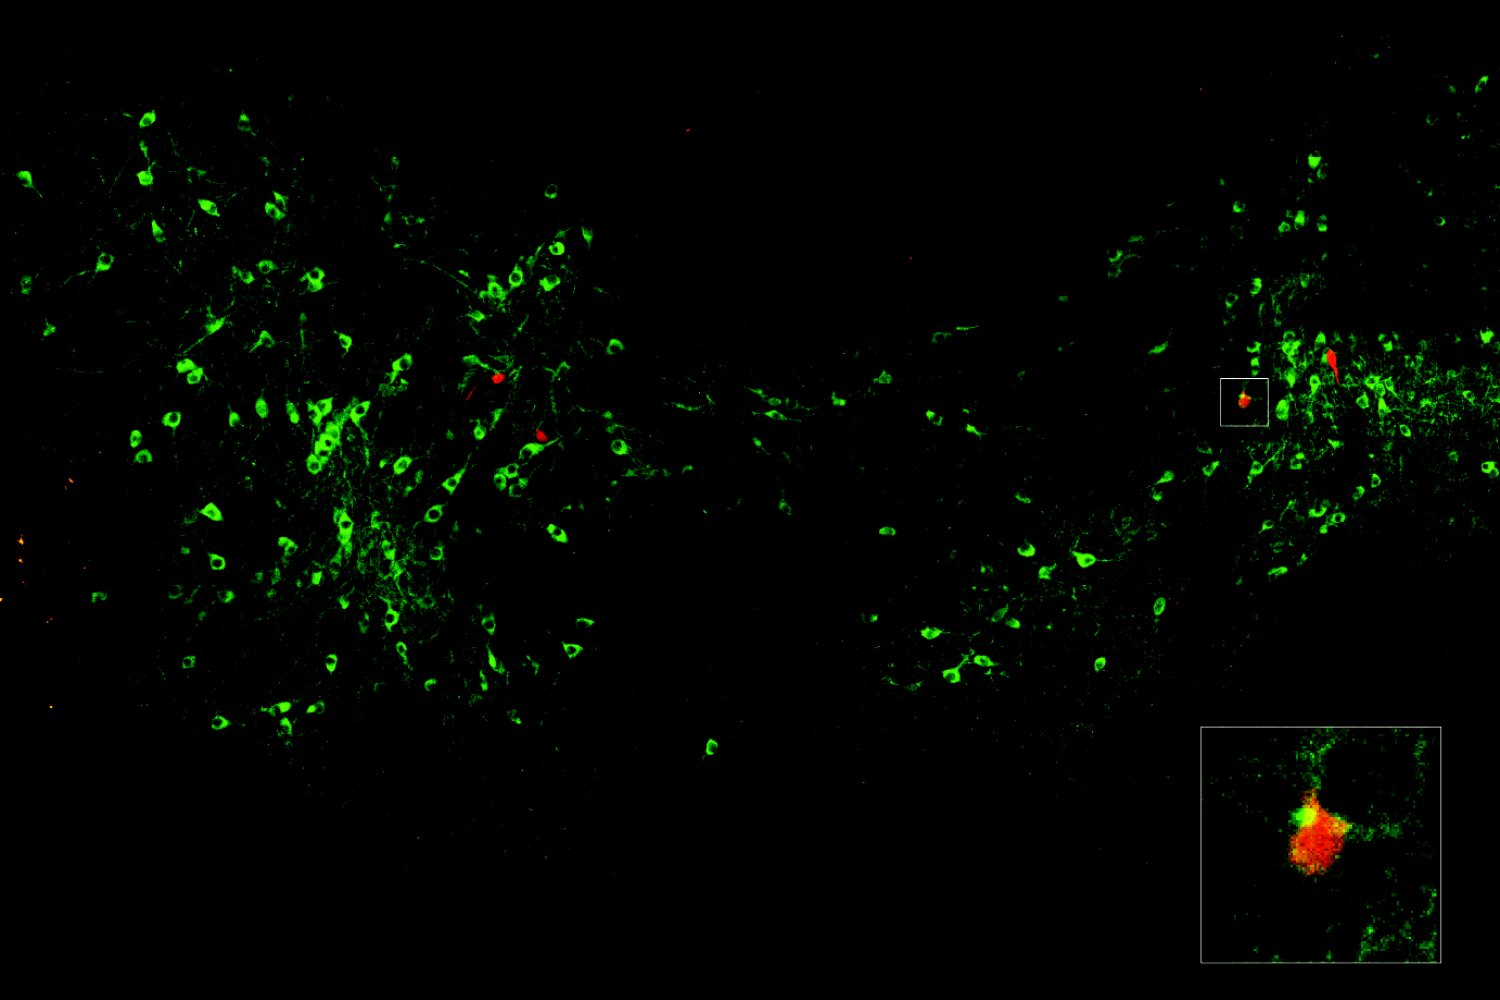

Dopamine signals when a fear can be forgotten

Dopamine signals when a fear can be forgotten

Dopamine signals when a fear can be forgotten

Dopamine signals when a fear can be forgotten

Dopamine signals when a fear can be forgotten